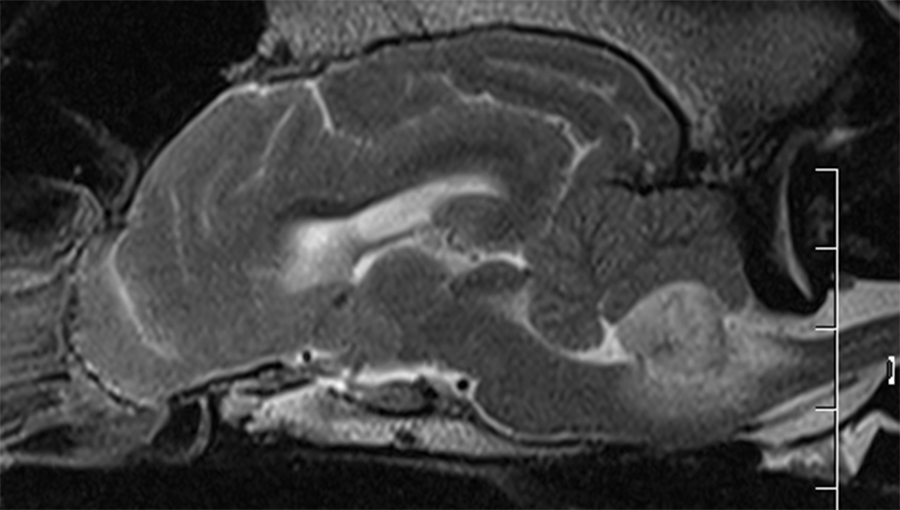

Cerebellar infarct

Cerebellar mass